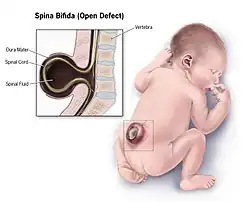

- Spina bifida aperta

- Aperta bedeutet „offen, sichtbar“. Es werden drei Formen dieser Spaltbildung (Rhachischisis)[3] unterschieden:

- Meningozele: Eine im Vergleich mit den anderen beiden Typen einfache, leichte Form der Spina bifida aperta ist die Meningozele. Dabei wölben sich nur die Rückenmarkshäute (= Meningen) durch einen Wirbelbogenspalt unter der Haut vor. Die dabei entstehende Blase (= Zyste) ist sichtbar. Sie kann operativ entfernt werden, was 1777 erstmals erfolgreich Held in Gießen gelang.[4] Es entstehen keine Beeinträchtigungen, denn das Rückenmark ist in seiner üblichen Lage und nicht geschädigt.

- Myelomeningozele: Bei dieser schwereren Form liegt eine Spaltbildung in der Wirbelsäule vor (Zele = Bruch) und durch diesen Spalt treten Teile des Rückenmarks (= Myelon), der Rückenmarkshäute (= Meningen) und Nerven in einer Blase (= Zyste) sichtbar nach außen hervor. Dadurch verlieren die Nervenstränge an der betroffenen Stelle ihren Schutz, und es kommt zu Schädigungen. Der beschriebene Vorfall kann operativ durch Hirnhaut überhäutet werden.

- Myeloschisis: Dieser Begriff wird häufig für besonders schwere Befunde einer Spina bifida aperta verwendet, bei denen das Nervengewebe an der betroffenen Stelle sichtbar völlig freigelegt und nicht von Haut oder Bindegewebe bedeckt ist.

Nachgeburtlich ist die Diagnose der Spina bifida aperta sofort möglich durch die sichtbare Fehlbildung am Rücken, die oft im Bereich der Lendenwirbelsäule und des Kreuzbeins, seltener im Bereich der Brust- und Halswirbelsäule zu finden ist.